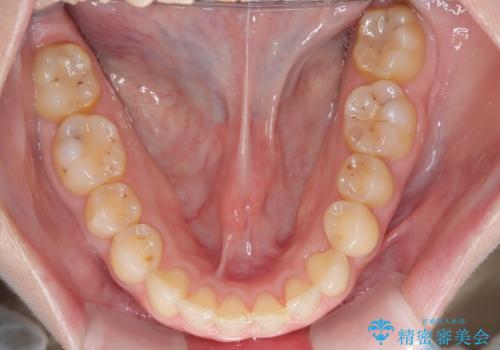

【インビザライン】前歯の凸凹を治したい。

- 前歯の凸凹を主訴に来院されました。

深い噛み合わせも同時に治療を行う計画を立て、インビザラインを使用して歯並びの改善を行うことができました。

叢生改善のために遠心移動とIPRを行なっています。